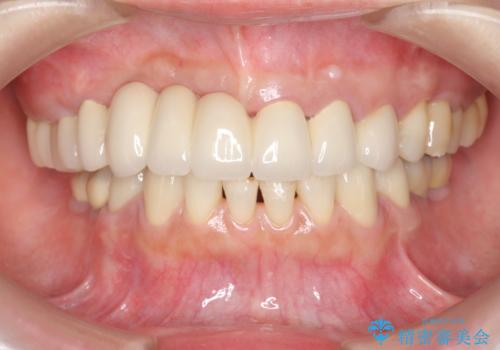

咬合性外傷による歯槽骨吸収 ブリッジ補綴

保存の難しい歯の抜歯、保存できる歯の歯周病治療、欠損部位の歯槽堤形態回復を含めブリッジによる安定した咬合機能回復を計画します。

- 90万円 (仮歯×9 メタルボンドクラウン×9)費用は治療当時の料金となります

ブリッジは欠損した部位に臨在する歯を削り、被せなければいけないというデメリットがありますが反面噛む力が強い場合連結することで強大な咬合力に対抗できるというメリットも存在します。